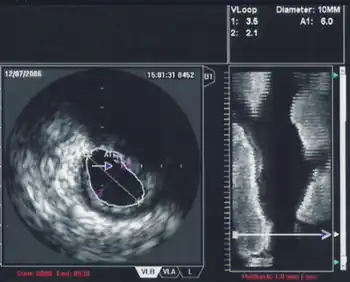

3D Echocardiography

3D TEE is a technology developed to improve upon the limitations of 2D tomography. With the introduction of the matrix TEE probe, 3D TEE can collect real-time 3D images that provide a comprehensive view of the heart structures, leading to better understanding and decision making during cardiac procedures. The technique acquires a volumetric data set and displays it in custom orientations, allowing for greater depth and understanding of heart structures compared to 2D echocardiography.[7]

Contrast Echocardiography

The introduction of ultrasound contrast agents for contrast echocardiography has significantly improved the usefulness of echocardiography in diagnosing and assessing coronary artery disease.[8] Ultrasound contrast is used for assessing left ventricular ejection fraction at rest and during stress echocardiography. Contrast echocardiography can simultaneously assess regional myocardial function and perfusion, allowing for the non-invasive diagnosis of coronary artery disease. It has several advantages compared to other non-invasive imaging techniques, such as being performed without radiation exposure and potential nephrotoxicity. Contrast echocardiography requires intravenous administration of an ultrasound contrast agent during contrast specific ultrasound imaging.[8]